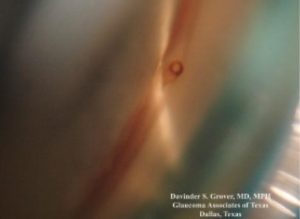

Figure 1. XEN45 gel stent as viewed by gonioscopy. Photo courtesy of Dr. Davinder Grover

XEN gel stent is an FDA approved device developed by Dr. Rohit Varma which allows passage of aqueous humor from the anterior chamber to the subconjunctival space.1 The stent, about the length and width of an eyelash, is made from a hydrophilic collagen-based gelatin material which allows it to be biocompatible and highly flexible once inserted. Preloaded in a disposable XEN injector, the device can be placed in an ab interno fashion by means of a self sealing clear corneal incision or now via an ab externo fashion where it is inserted through a small transconjunctival incision.

Similar to trabeculectomy, XEN stent surgery is only successful if a conjunctival bleb is created perioperatively and carefully maintained postoperatively. Anti-scarring agents such as Mitomycin C and fluorouracil (5FU) are utilized during and following the procedure to counteract conjunctival scarring which threatens proper filtration. Encapsulation of the XEN bleb is a complication that needs an immediate diagnosis so that proper bleb management efforts can be employed. In a multicenter prospective study conducted by Grover the postoperative complication most reported was conjunctival bleb scarring requiring needling.7 Careful gonioscopy can also ensure that the XEN stent is properly placed as the device can occasionally become kinked or obstructed by iris anatomy.